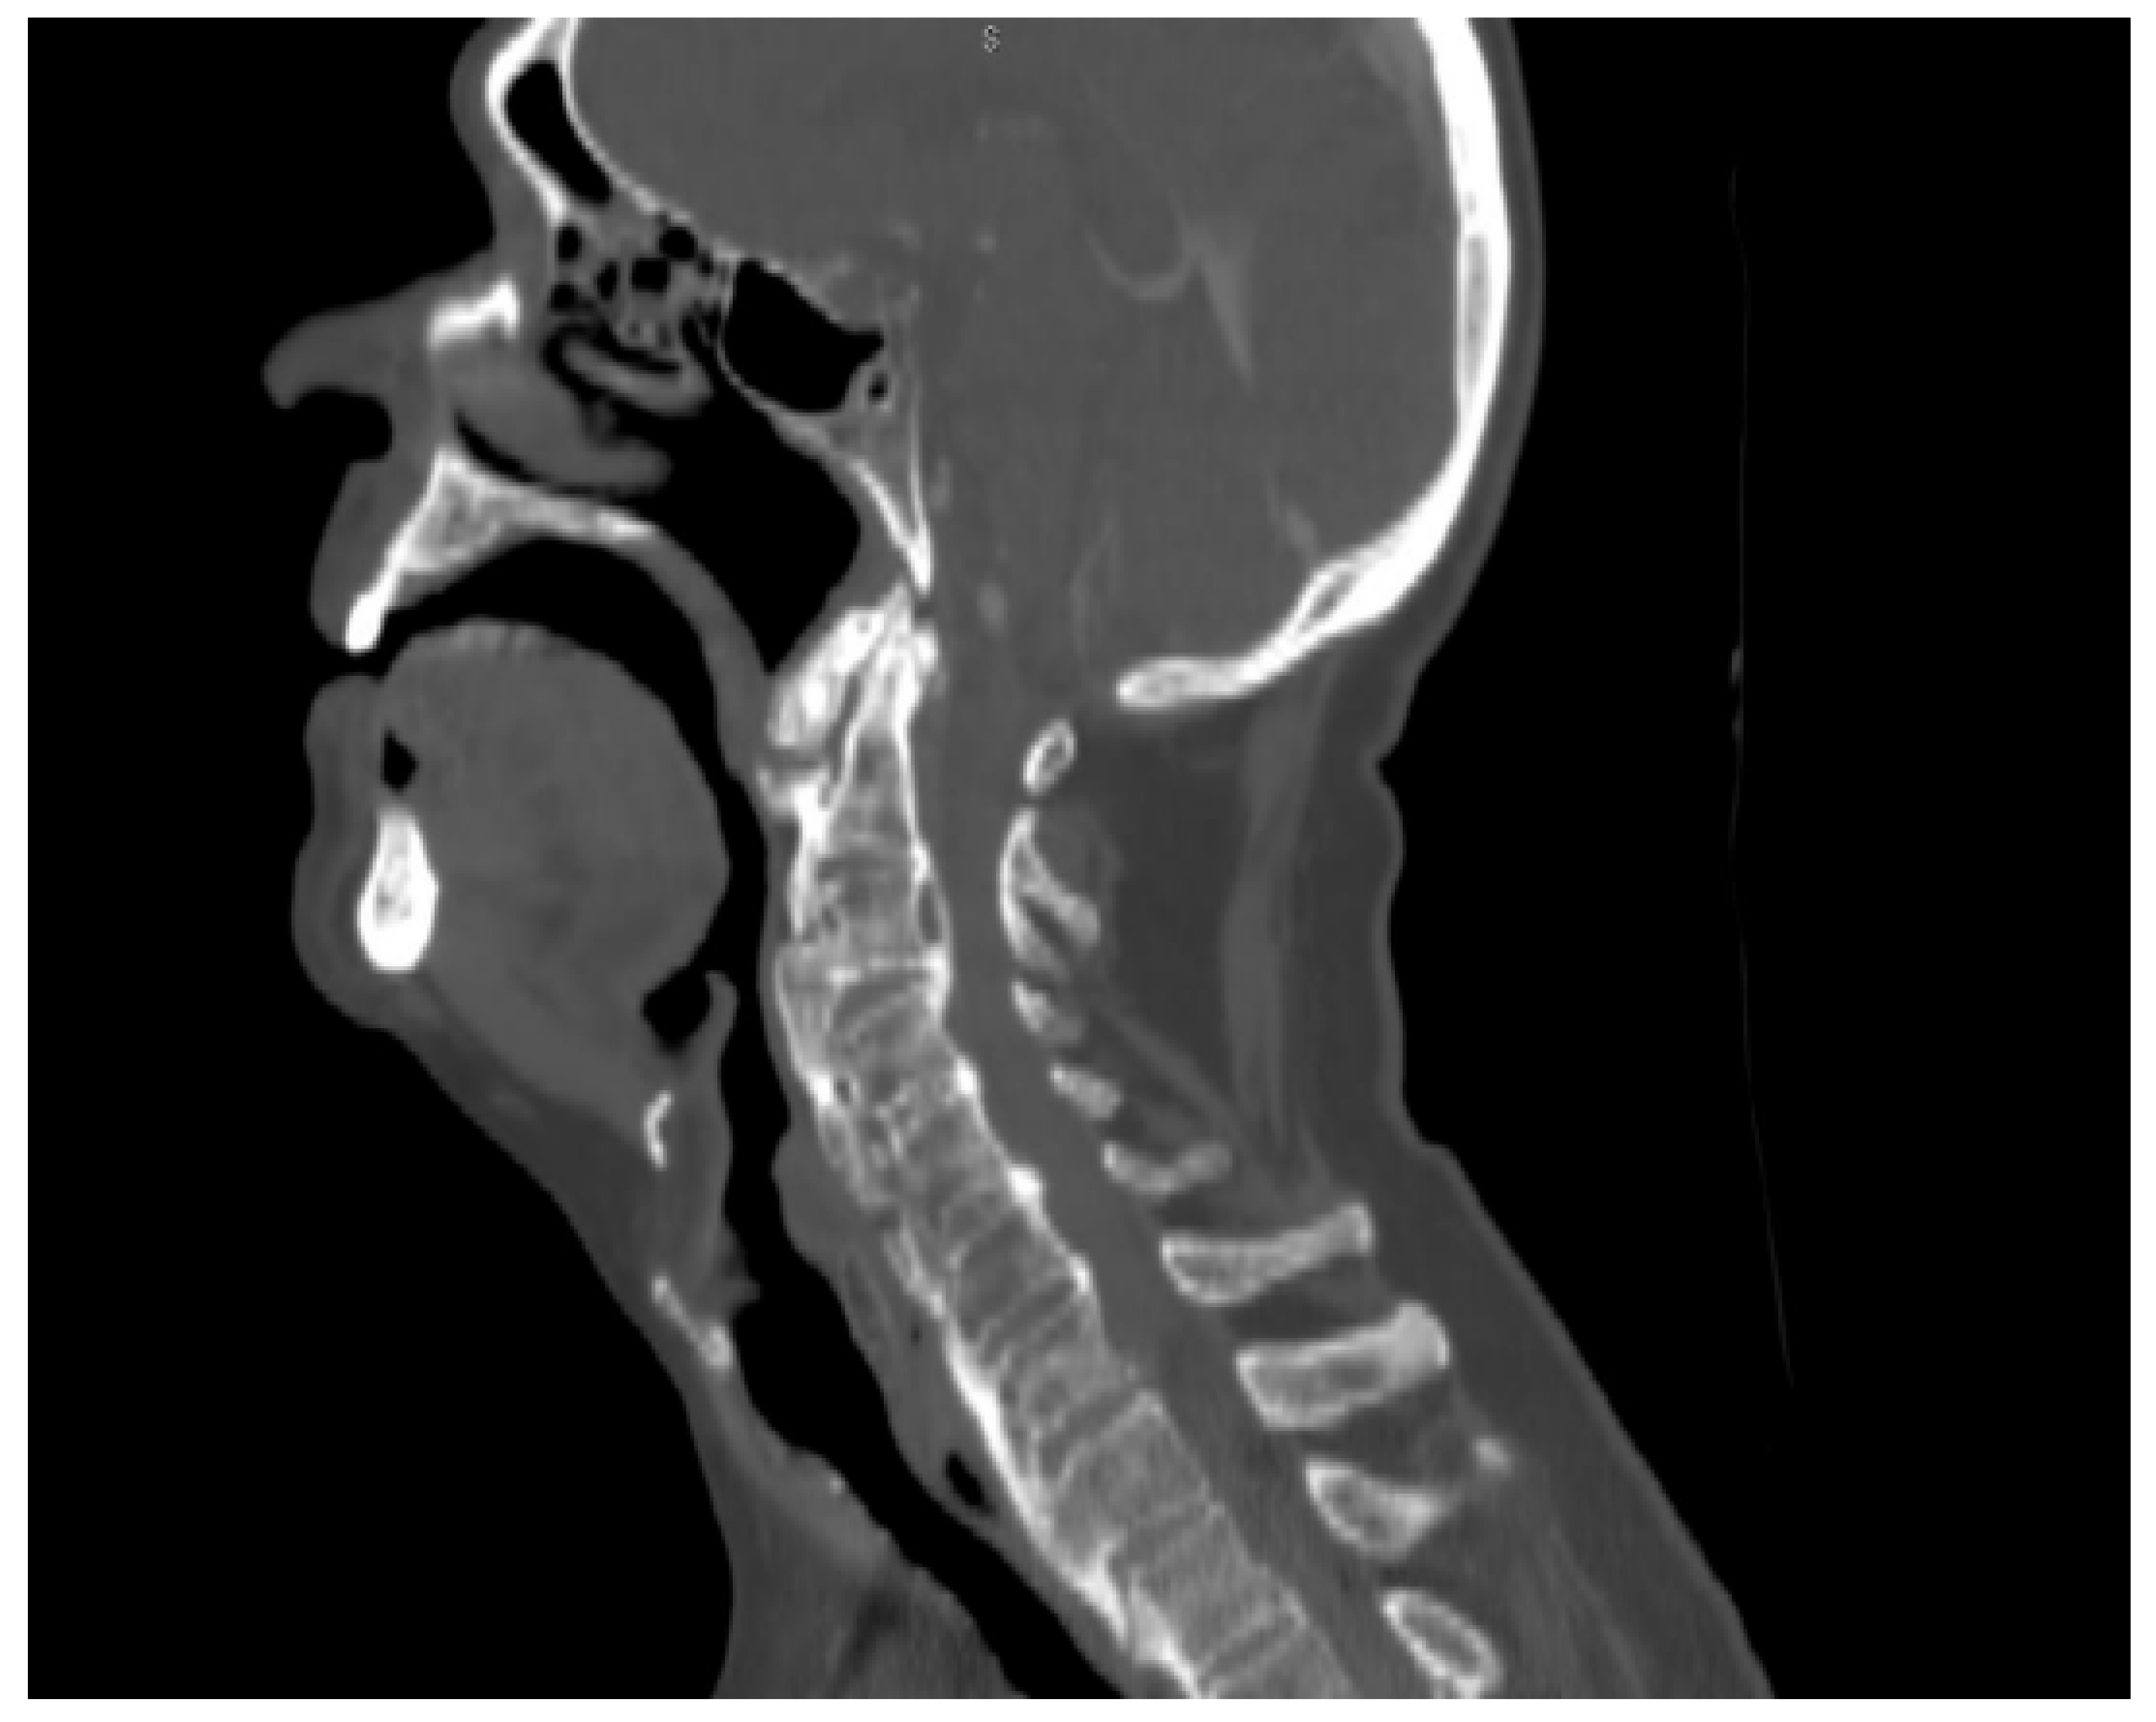

He also complained of mild pain at the back of the neck, which was associated with scapulohumeral impairment. Evaluation through flexible (fiber-optic) laryngoscopy revealed the presence of a mass protruding from the posterior wall of the rhinopharynx causing a critical narrowing of the oropharyngeal lumen and the laryngeal aditus. Mucosa appeared normal with no other abnormalities detected (Figure 1).

Figure 3. A bulging posterior pharyngeal wall contacting the base of the tongue and the epiglottis.